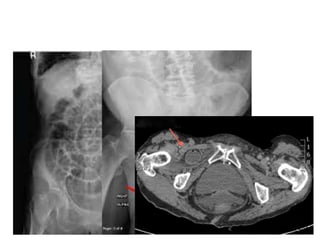

Obturator hernia • Hyperesthesiaor pain in the medial thigh or in the region of the greater trochanter • Relieved by thigh flexion • Worsened by medial rotation, adduction, or extension at the hip • Typically an elderly, frail lady who had lost signifcant body fat thus opening up the obturator foramen • Management – Elective • Laparoscopic repair – Emergency • Laparotomy (bowel gangrene common)